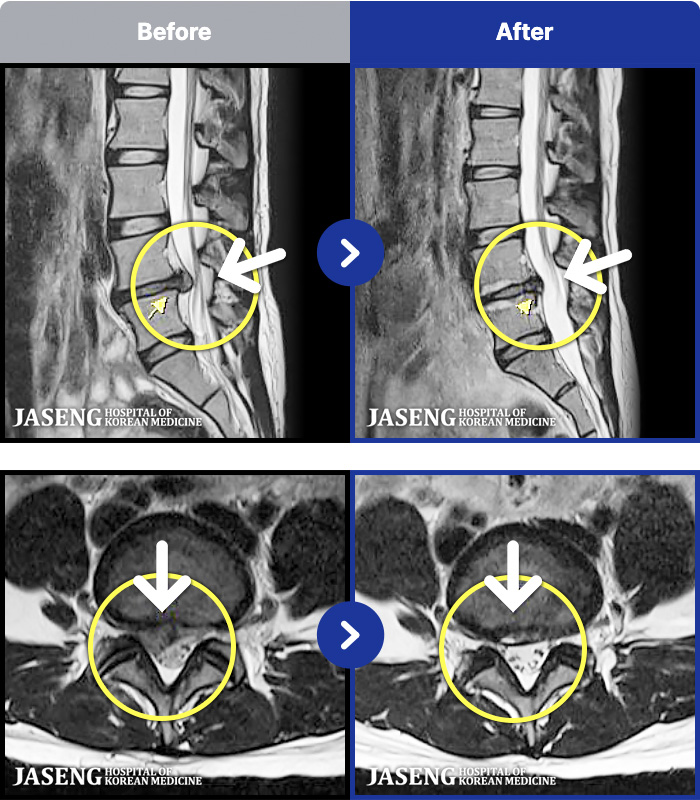

97 MRI ũ ʸ Ȯϼ.

ȯںп Ǹ ǿ ԿǾ, ο ġ ۿ Ƿ ġḦ Ͻñ ٶϴ.